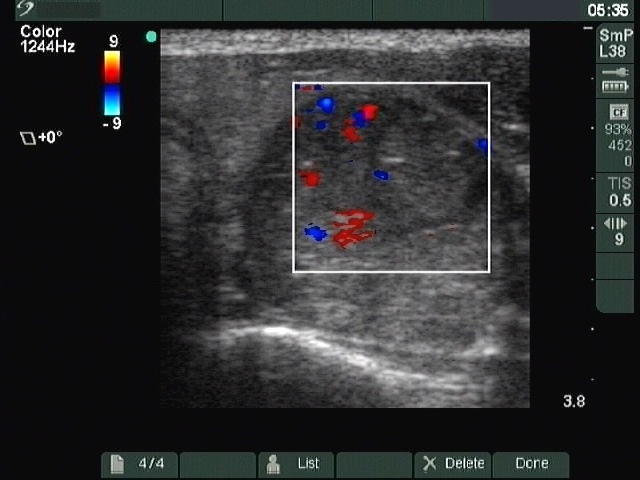

Ultrasonography: The left lobe contained a mixed nodule with increased intranodular blood flow.